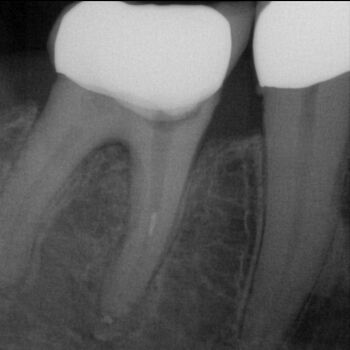

Fall 3: Obliterierte Kanäle

DVT-Endodontologie-Fallbeispiele in der Zahnarztpraxis Dr. Buscot & Kollegen in Braunschweig

Ausgangssituation

Kontrolle nach Wurzelfüllung